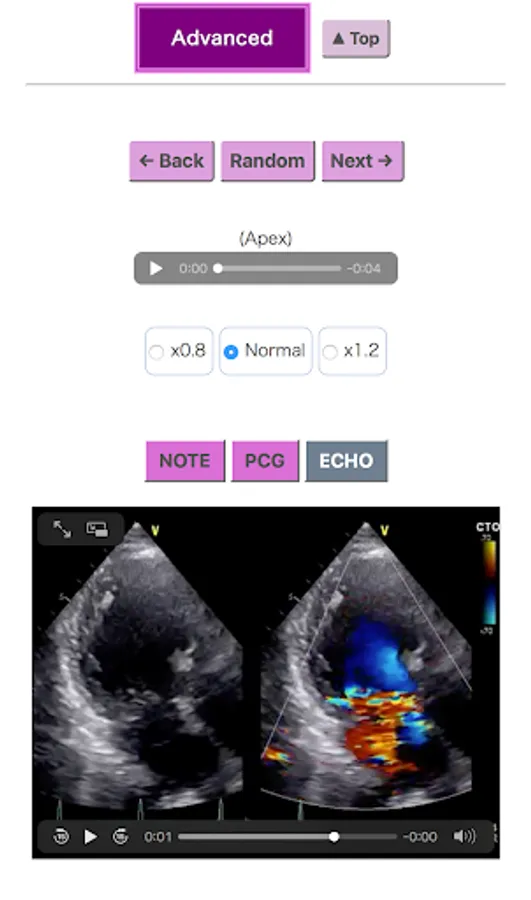

This app is designed to describe the pleasure of communicating with the heart; 150 phonocardiograms (PCGs) were selected from more than 5,000 recordings: Each PCG is shown with sound, and 50 PCGs have both sound and echocardiography. The history of the stethoscope and trivia for cardiac auscultation are also included.